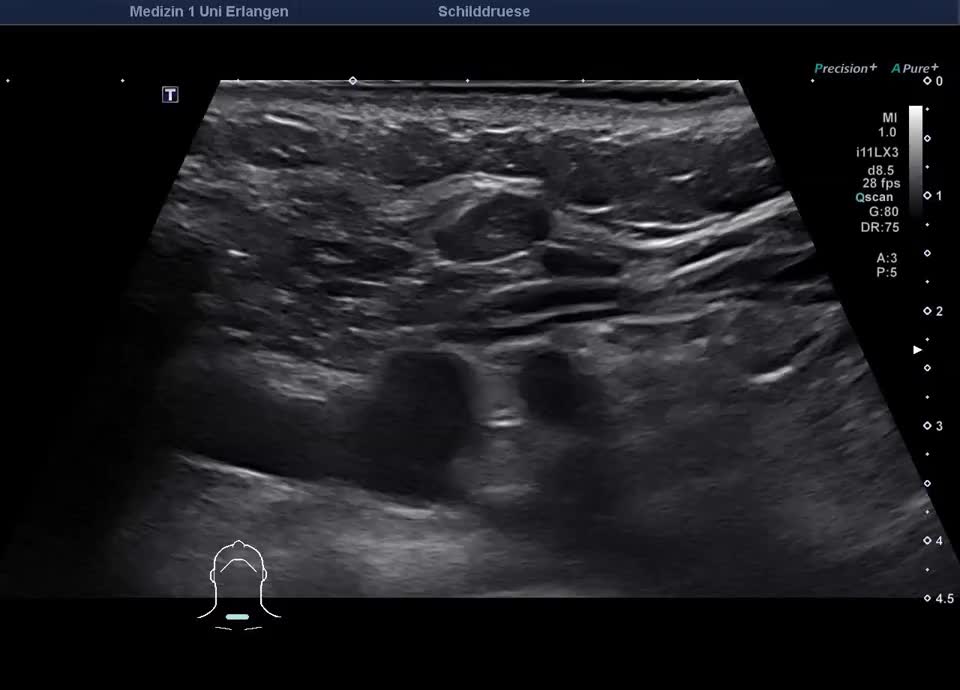

36-jähriger Patient mit Tremor, Tachykardie, Exophthalmus und Gewichtsverlust. Sonographisch stellt sich die Schilddrüse beidseits mit echoarmer inhomogener Parenchymstruktur dar. Gesamtvolumen 20,5 ml. Farbdopplersonographisch hypervaskularisiert. Laborbefunde: basales TSH erniedrigt, T3/fT4 erhöht, TRAK positiv. Befundkonstellation vereinbar mit M. Basedow. Unter Therapie mit Thiamazol und Propranolol beschwerdefrei. Bei Verlaufskontrolle zwei Jahre später sonographisch echoreiches minimal inhomogenes Parenchym bei normalem Volumen (15 ml).